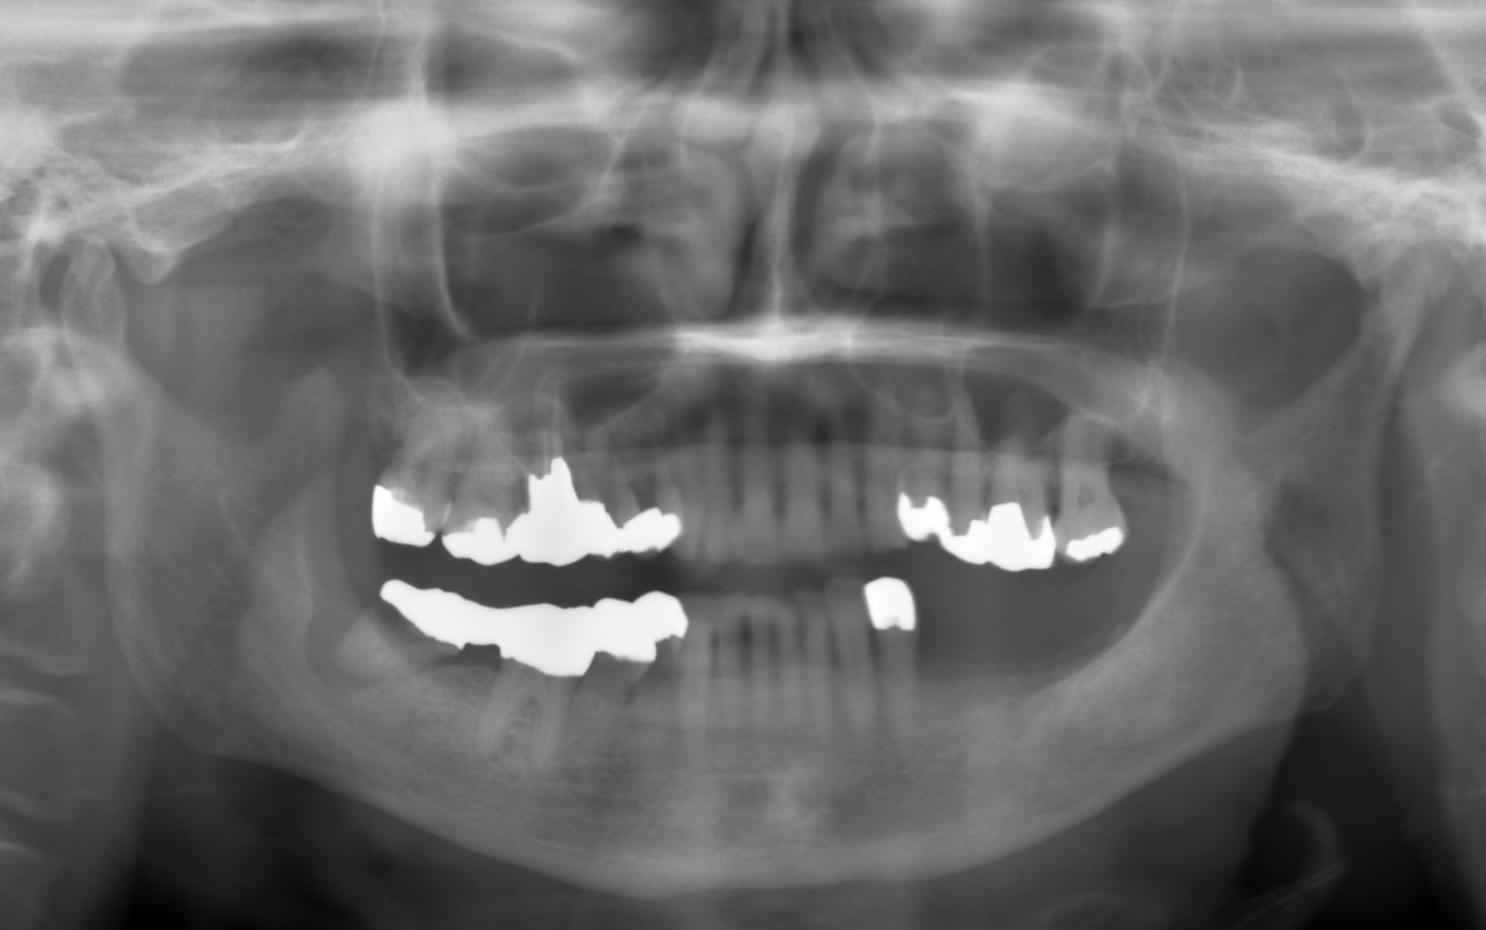

左下奥歯3本欠損部分にインプラント3本

1、術前診断、治療計画

他院で治療中の患者様です。

左下がかなり大きく吸収してます。

インプラントを希望していますが

埋入するだけの神経までの骨の厚みがなく

人工的に顎の骨を再生する処置(GBR)を勧められています。

術前のCT診断の結果は

下顎管神経までが6~7ミリしかありません。